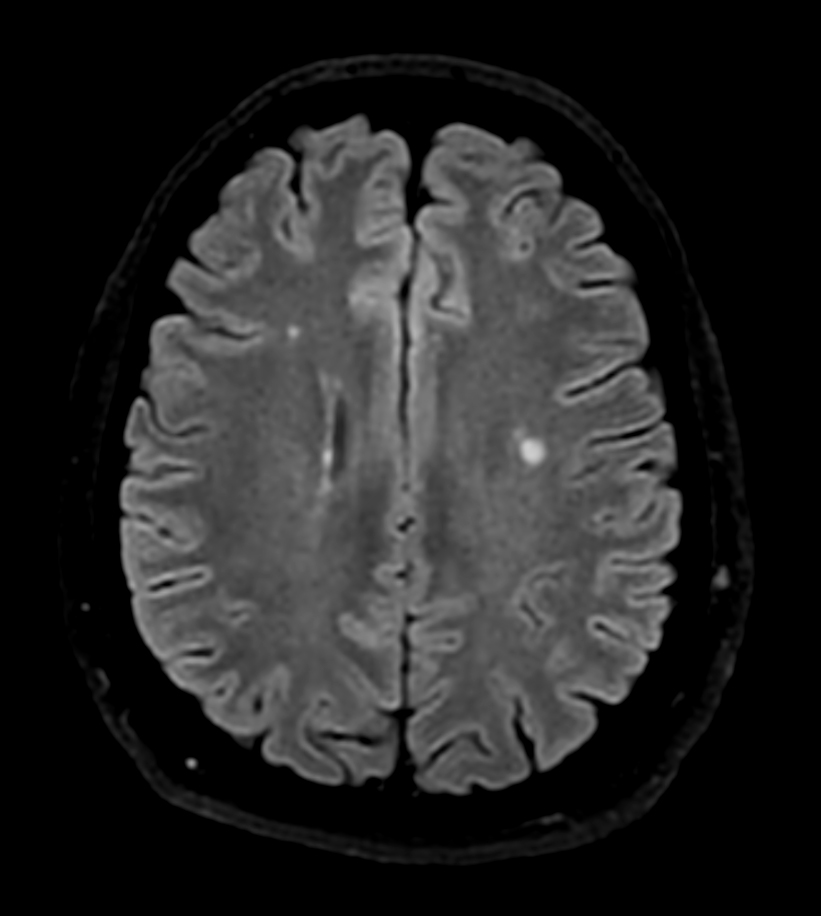

Axial SWIp